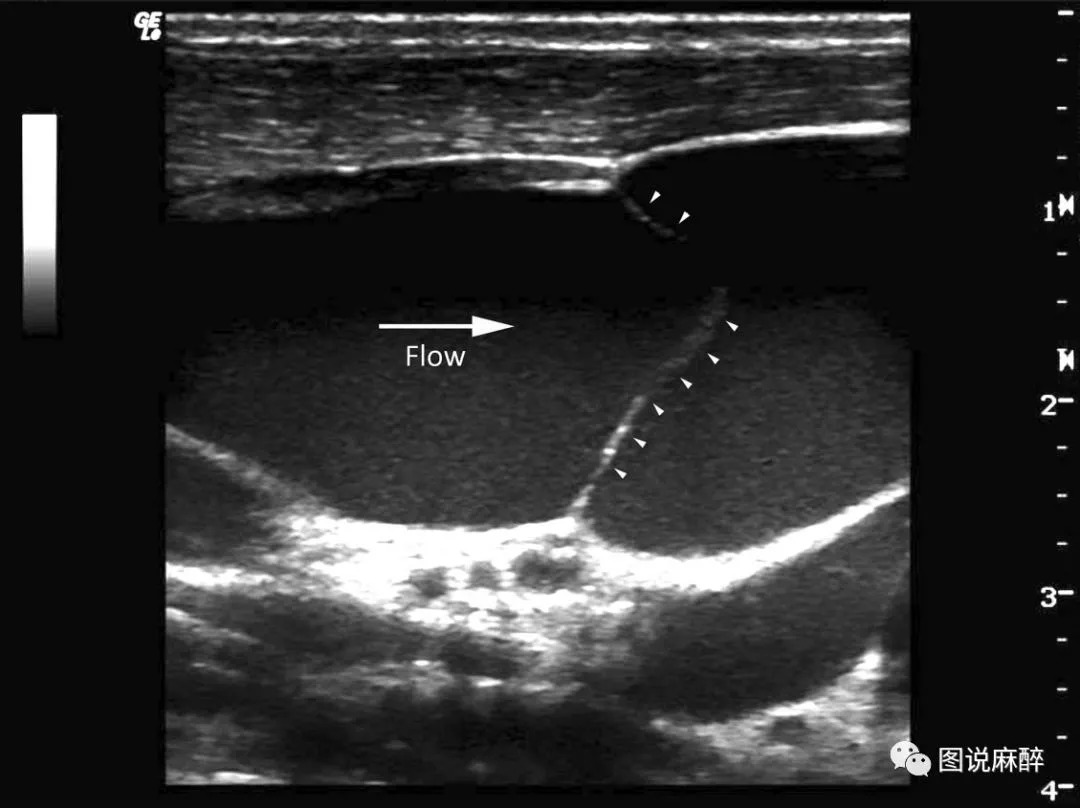

今天就到这里,最后来一张ANESTHESIOLOGY杂志2010年发的高清大图。让我们脑中留下印象,下次钢丝遇到阻力了多留个心眼,超声看一下。

声像图上颈静脉瓣呈带样强回声,根部附着于静脉壁上,瓣膜游离缘指向心脏方向。

颈内静脉瓣可以承受100mmHg的压力,作用是防止右心房血液逆流入脑,例如在咳嗽和行Valsalva动作的时候。